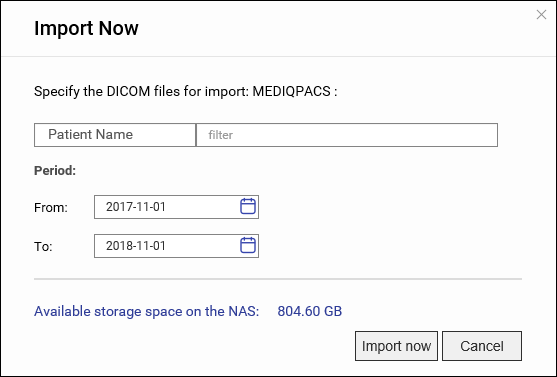

用户可按计划将 DICOM 图像导入到基于 NAS 的 PACS 服务器,也可以将它们直接导入。

手动导入图像